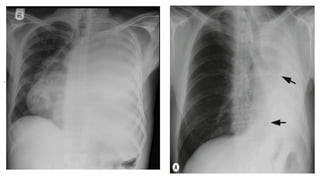

Left lower lobe collapse

● The left lung field appears much darker than normal and the heart shadow will appear much whiter

than normal.

● If you look carefully you can see a white triangle behind the heart

Right lower lobe collapse

There is a opacity immediately above the diaphragm causing a loss of its outline. On the lateral film there is a

white triangle at the lower posterior part of the lung field.Note how the outline of the right heart border is

maintained.